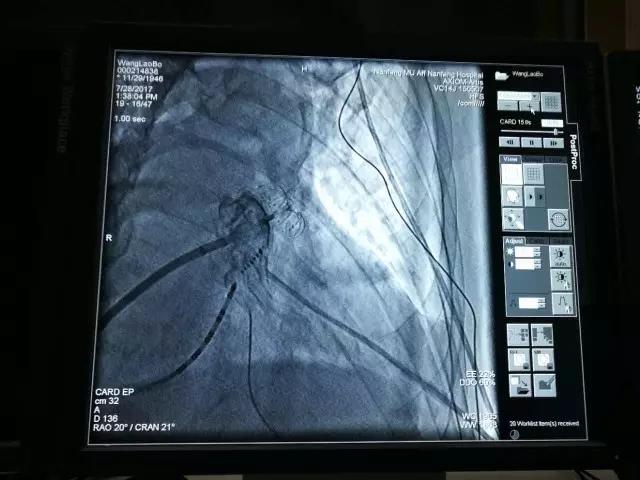

(左心耳封堵器释放后造影显示:封堵器封堵完全,无残余分流,对二尖瓣及左上肺静脉均无影响)